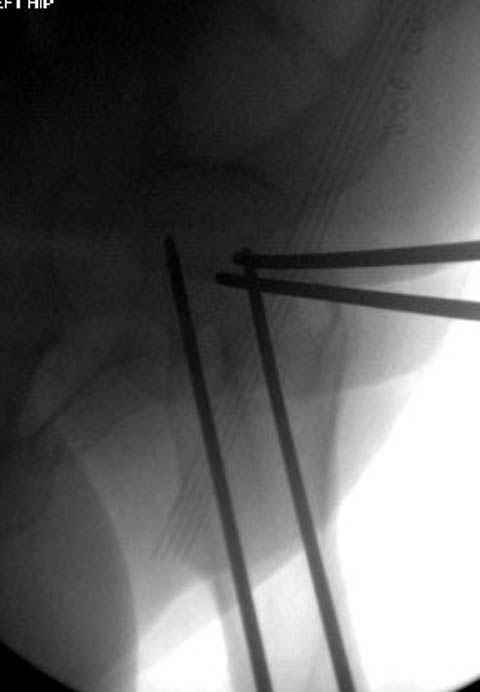

В данный момент скелетное вытяжение получается через перелом шейки, а

фиксированный перелом шейки будет участвовать в процессе вытяжения через

канюлированные  шурупы.

Имя     : 6 fem neck CRM.jpg

Тип     : image/jpeg

Размер  : 24442 байтов

Описание: отсутствует

Url     : http://weborto.net:8080/pipermail/ortho/attachments/20080116/651190cc/attachment-0011.jpg